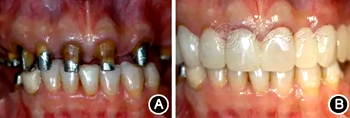

口腔衛(wèi)生狀況一般,菌斑指數(shù)0~2,鄰面少量軟垢;牙齦齦緣鮮紅、水腫、質(zhì)軟,出血指數(shù)2~3,余牙牙齦輕度水腫,出血指數(shù)0~2;全口探診深度2~3 mm,個別位點探診深度達(dá)4~5 mm,鄰面可探及附著喪失;未查及牙齒松動及根分叉病變;烤瓷固定橋修復(fù),冠邊緣密合度欠佳,位于齦下1~2 mm;、唇側(cè)崩瓷,邊緣暴露;上前牙牙齦線不協(xié)調(diào);缺失,右下后牙可摘局部義齒修復(fù),固定橋修復(fù);近中面銀汞充填,近中懸突及繼發(fā)齲;上前牙覆蓋下前牙牙冠的1/2~2/3(圖1)。

圖1 患者初診時臨床照片 A:正面微笑像;B:正面口內(nèi)像